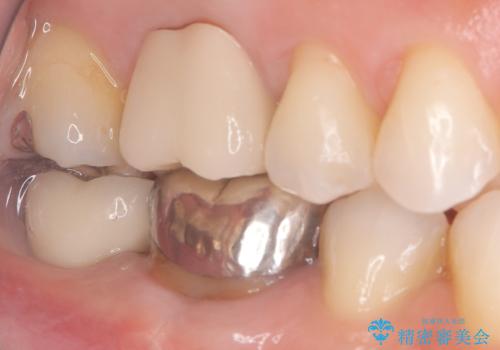

- 患者様は、奥歯を失ったことで「しっかり噛めるようになりたい」とのご希望で来院されました。ブリッジや入れ歯ではなく、インプラントによる治療を希望されたため、精密検査を実施。骨の状態が良好であったため、1回法(1回の手術でインプラント埋入とヒーリングアバットメント装着を同時に行う方法)を選択しました。これにより、外科的負担を軽減しながら、治療期間の短縮も図ることができました。

手術は1回で完了し、局所麻酔下でインプラントを埋入した後、ヒーリングアバットメントを装着。術後の腫れや痛みも少なく、患者様はスムーズに日常生活へ戻ることができました。約3ヶ月の治癒期間を経て、セラミッククラウンをセット。見た目の美しさはもちろん、天然歯に近い噛み心地を実現しました。患者様からは「違和感なくしっかり噛める」とご満足の声をいただきました。